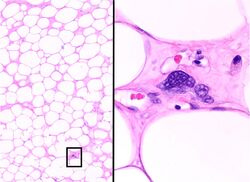

Histopathology of liposarcoma, H&E stain:[1]

ALT/WDL, adipocytic/lipoma-like. At low magnification, the tumor mostly contains adipocytes that appear benign and mature, but high magnification of one fibrous band shows abnormal spindle-shaped cells with enlarged, heterochromatic nuclei.

Histopathologically, ALT/WDL tumors are divided into adipocytic/lipoma-like, sclerosing, and inflammatory variants with adipocyte/lipoma-like being the most common. Adipocytic/lipoma-like ALT/WDL tumors consist of lobules of mature fat cells variably intersected with irregular fibrous septa (see the adjacent H&E stained photomicrograph). Sclerosing ALT/WDL tumors, the second most common variant, develop primarily in the retroperitoneal and paratesticular areas; it consists of scattered, atypical stromal cells within a collagenous (i.e. collagen-containing) stromal tissue background. Rare vacuole-containing lipoblasts populate this tissue. Inflammatory ALT/WDL tumors are the rarest variant. they occur most frequently in the retroperitoneum and consists of chronic inflammatory cells, e.g. lymphocytes and plasma cells plus occasional lymph node-like follicles interspersed throughout a tissue background containing fat cells.[14]